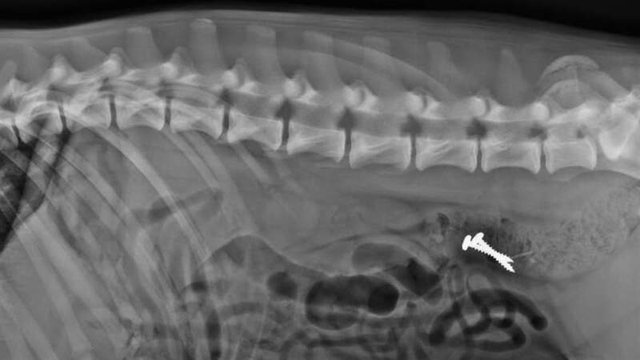

Una atención temprana puede hacer la diferencia entre una solución sencilla y una cirugía mayor. El veterinario evaluará el estado general y probablemente realizará estudios como:

A veces solo vemos los síntomas, pero no el "crimen". Aun así, ¡no lo ignores! Lleva a tu mascota a revisión cuanto antes. Con estudios de imagen y un buen examen clínico se puede detectar qué está pasando.